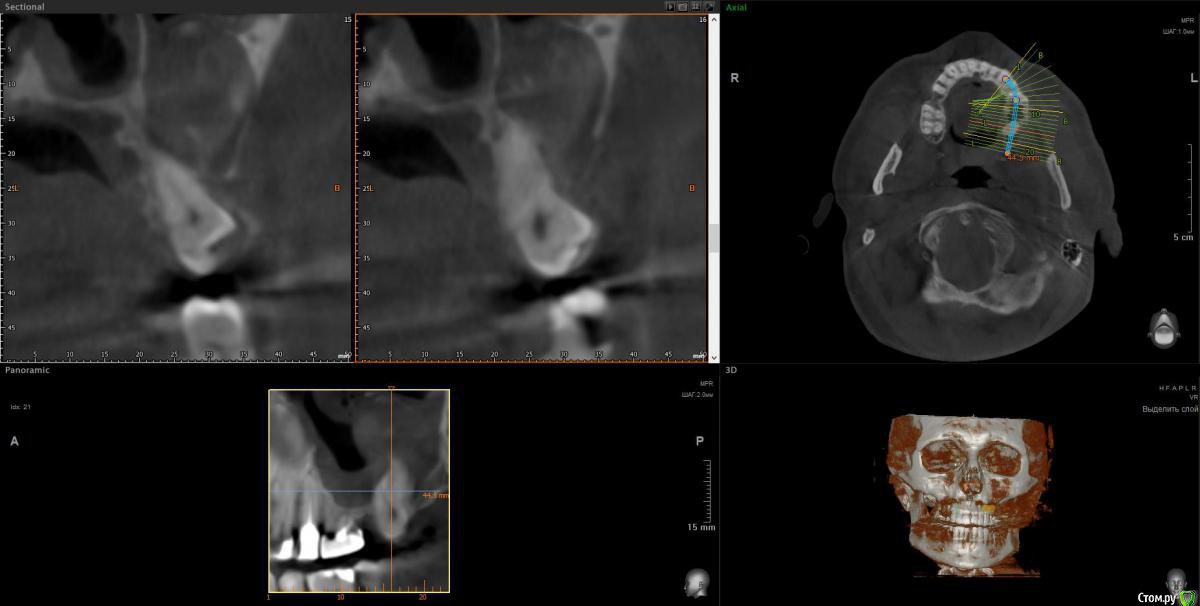

wladdX Опубликовано 5 марта, 2019 Поделиться Опубликовано 5 марта, 2019 Корональная проекция Сагиттальная справа Сагиттальная слева 16 26 28 Ссылка на комментарий

kramer Опубликовано 5 марта, 2019 Поделиться Опубликовано 5 марта, 2019 В общем скачал я КТ. Что касается зуба 26, да, там есть признаки воспаления вокруг корней, лечить / удалять зависит от состояния тканей зуба и возможностей врача. Но лично мне не кажется, что этот зуб играет главную роль в возникшем гайморите. Обратите внимание, в области 8 зуба (см. срез) внутри пазухи есть некий очаг, содержащий неоднородные по плотности элементы (более светлые включения, а выше пузырьки воздуха). Снимок не особо четкий, но такое ощущение, что в области 8 зуба вообще нарушена целостность боковой стенки пазухи. Кроме того, с правой стороны все зубы в порядке, а явления гайморита тоже имеются (там вообще почти вся пазуха забита). Соустья с носом закрыты. В общем, в данной ситуации я бы более детально обследовал 8 зуб, если там все нормально, то пусть ЛОРы эндоскопически лезут в пазухи и убирают это все. Ссылка на комментарий